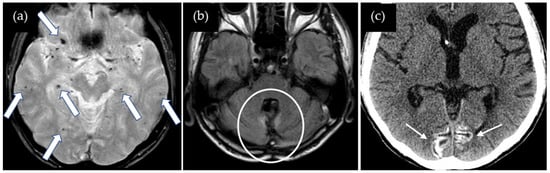

A 47-year-old man presented with dysarthria and transient symptoms of weakness and numbness in the left upper extremity. He had a history of a cerebellar tumor that had been removed at the age of 11 years. Use of cadaveric dura mater, Lyodura, was confirmed, although any other detailed information about surgical procedure was not available. Radiation therapy was not performed. He had no history of hypertension or familial CAA. T2*-weighted images showed no cSS in the right precentral gyrus or other gyri, while multiple lobar CMBs were detected mainly in both cerebral hemispheres, with several CMBs also observed in the cerebellum (Figure 3). The CAA-SVD score was 2 based on the previous literature [5], consisting of two points for lobar CMBs, zero points for cSS, zero points for CSO-PVSs, and zero points for WMH. CT showed prominent cortical calcifications in both occipital lobes, which were not visible on the T2*-weighted image. Neither CSF examination nor amyloid PET was performed. Thus, this case was considered a possible iCAA based on the criteria [1].

Figure 3.

(a) T2*-weighted image shows no cSS in the right precentral gyrus or other gyri, while multiple lobar CMBs (arrows) are detected in both cerebral hemispheres; (b) 2D FLAIR shows postoperative changes in the cerebellum (circle); (c) CT shows prominent cortical calcifications in both occipital lobes (small arrows).